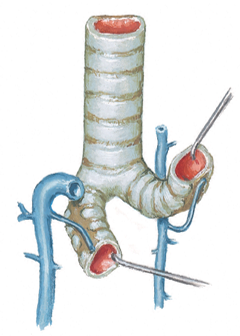

what is a thoracentesis? what do you want to avoid when you insert the needle? overall, where do you wanna put the needle?

below

- Procedure to remove fluid from pleural cavity

- Avoid damage to intercostal structures (and lung) when inserting needle

put the needle on the superior margin of the rib...avoids hitting the VAN's